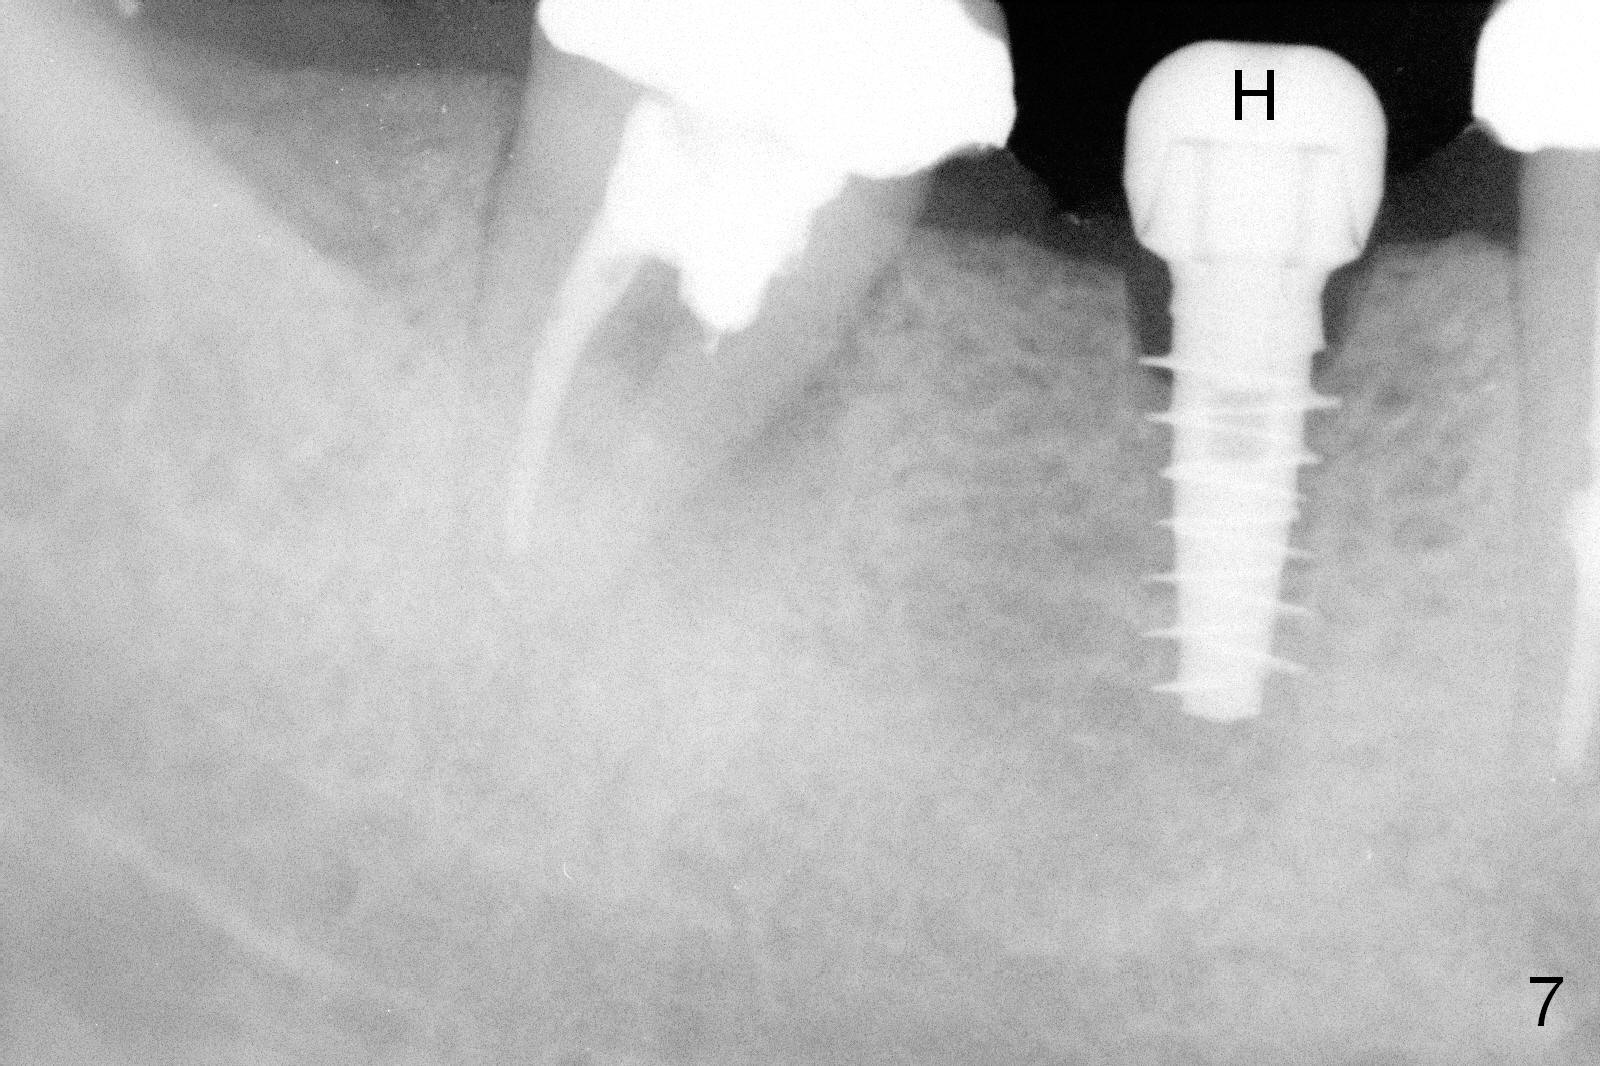

CBCT was taken (Fig.1,2 (P: pontic; S; submandibular fossa)) several months prior to #29 and 31 RCT and #31 porcelain chip (Fig.3). When the bridge is sectioned, the pointed ridge at #30 (Fig.1) is confirmed (Fig.4,5). After flattening the ridge until 6 mm buccolingually (Fig.6 arrowheads), osteotomy is initiated with 1.6 mm drill at 9 mm; there is 2.5 mm clearance from the superior border of the Inferior Alveolar Canal (red dashed line). A 4.5x9(1) mm Magicore is placed with 35 Ncm (insertion torque) after 4.3 mm Magic Drill; a 4.5 mm healing abutment (Fig.7 H). An error occurs because of using 1 mm cuff of the Magicore. Ideally 3 or 4 mm cuff should have been used because of reduction of the ridge by ~ 3 mm (Fig.2). The result of the error is failure of placing the implant at the desirable depth (<9 mm). The coronal threads are exposed and have to be covered by bone graft (autogenous bone and allograft (.5-1.5 mm) (Fig.8 *), followed by collagen dressing. Extra suturing is done to securely close the wound (Fig.9), followed by periodontal dressing (data not shown).